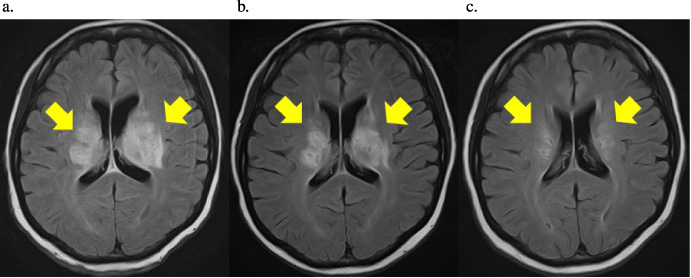

Case presentation: Our patient had a history of BD and was asymptomatic. She was diagnosed with human epidermal growth factor receptor 2-positive breast cancer by core needle biopsy and was administered neoadjuvant chemotherapy. After four courses, in addition to the aggravation of the existing adverse events, headache, fever, dysarthria, and muscle weakness in the upper left and lower extremities appeared. On admission, she was diagnosed with acute NBD, and steroid therapy was initiated. After her symptoms improved gradually, she was discharged. Then, she underwent mastectomy and axillary lymph node dissection for breast cancer. Trastuzumab and pertuzumab plus tamoxifen were administered postoperatively. Two years postoperatively, no recurrence of breast cancer and NBD was noted.